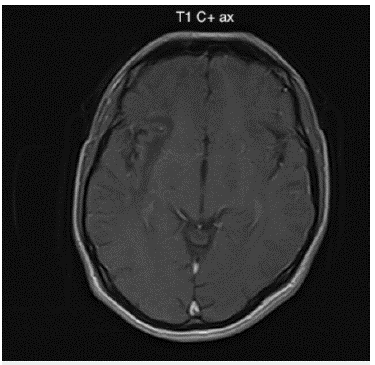

Ante el cuadro clínico y los hallazgos descritos en el examen físico se realizó una imagen de resonancia magnética (IRM) cerebral contrastada (figuras 1-3) en la cual se documentó la presencia de hiperintensidades extensas a nivel subcortical que comprometían la sustancia blanca hemisférica cerebral derecha con una distribución en los lóbulos frontal, parietal y temporal. Adicionalmente, se observó compromiso de la sustancia blanca en la región frontotemporal izquierda que comprometía las fibras en U. No se identificaron áreas de sangrado ni tampoco la presencia de masas ni realces anormales con el medio de contraste.

Figura 2: Imagen de resonancia magnética cerebral contrastada corte axial en secuencia FLAIR: Lesiones hiperintensas asimétricas de la sustancia blanca subcortical difusa de predominio derecho, con compromiso en fibras en U yuxtacorticales. No genera efecto de masa ni realce con el medio de contraste.

Por medio de la IRM cerebral contrastada, especialmente en la secuenciación potenciada en T2 y recuperación de la inversión atenuada de fluido (FLAIR por sus siglas en inglés), fue posible identificar las lesiones típicas de la enfermedad. Se trata de lesiones múltiples bilaterales, hiperintensas, asimétricas, de morfología irregular, que comprometen la sustancia blanca subcortical y yuxtacortical del cerebro, incluyendo las fibras en U, delineando los bordes de la corteza sin producir efecto de masa ni realce con el medio de contraste 3,8,9. En la secuenciación potenciada en T1 estas lesiones se presentan hipointensas.